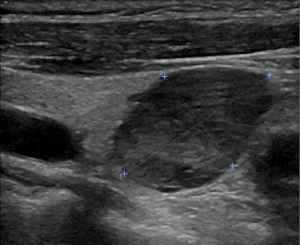

In this study, four patients with functional parathyroid carcinoma underwent preoperative ultrasound (Figure 1) and dual-phase technetium 99m sestamibi (99mTc-MIBI) parathyroid scintigraphy with single-photon emission computed tomography (SPECT)/computed tomography (CT) (Figure 2). The two patients with nonfunctional parathyroid carcinoma had preoperative ultrasound and CT scans (Figure 3). There were 2 cases where the tumors were located in the right neck and 4 cases in the left neck. On ultrasound examination, the smallest tumor measured 2.5 cm in diameter, while the largest was 11.4 cm, with five cases (83.33%) having diameters ≥3 cm (Table 2). Among the four patients with functional parathyroid carcinoma, preoperative PTH levels ranged from 269.8 to 6,012.3 ng/L, with three cases exceeding 10 times the upper limit of normal. All four patients had preoperative serum calcium levels above the upper limit of normal. In contrast, the two patients with nonfunctional parathyroid carcinoma had normal preoperative PTH and calcium levels (Table 2).

The diagnosis of parathyroid carcinoma is extremely challenging, especially preoperatively (18,19). Functional parathyroid carcinoma presents clinically with symptoms identical to those of hyperparathyroidism caused by parathyroid adenomas, making differentiation between the two difficult. Some researchers found that when PTH levels exceed 10 times the upper limit of normal (3) or when serum calcium levels are greater than 3 mmol/L in conjunction with a parathyroid tumor diameter larger than 3 cm, a diagnosis of parathyroid carcinoma should be highly considered (19). In this study, PTH levels exceeded 10 times the upper limit of normal in three cases (50%), and serum calcium levels were greater than 3 mmol/L with tumor diameters larger than 3 cm in two cases (33.3%). However, these characteristics are also present in many parathyroid adenomas and therefore cannot serve as the sole diagnostic criterion. Parathyroid carcinoma may appear as a larger tumor with a diameter often exceeding 3 cm or with unclear margins on ultrasound, CT, or magnetic resonance imaging (Figures 1-3). However, these features can also be observed in parathyroid adenomas. Thus, while imaging studies can help detect and localize parathyroid tumors, diagnosing parathyroid carcinoma based solely on imaging is extremely difficult (20). Most cases of parathyroid carcinoma are diagnosed through postoperative histopathological examination, as was the case with all six patients in this study.